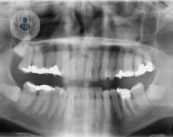

El cáncer oral: diagnóstico, causas y tratamiento

El cáncer oral es un tipo de cáncer sin una causa específica, aun así factores como el tabaco o el consumo de alcohol son el motivo más común de aparición. Conoce todos los detalles sobre esta patología gracias al cirujano maxilofacial, el Dr. Verrier Hernández.

Cáncer oral: importancia del diagnóstico y tratamiento precoz.

El Cáncer Oral puede afectar a cualquier estructura de la cavidad bucal. Según la OMS hay un incremento de 5.000 casos al año. El Dr. Palazón Tovar, experto en Cirugía Oral y Maxilofacial, te da todos los detalles para diagnosticarlo y tratarlo a tiempo.

Implantes dentales en el paciente oncológico

Los tratamientos para combatir cualquier tipo de cáncer existentes provocan distintos cambios en el cuerpo del paciente como puede ser la debilidad ósea. En el siguiente vídeo, el Dr. Navarro Vila nos explica de qué manera se aplican los implantes dentales en pacientes oncológicos.